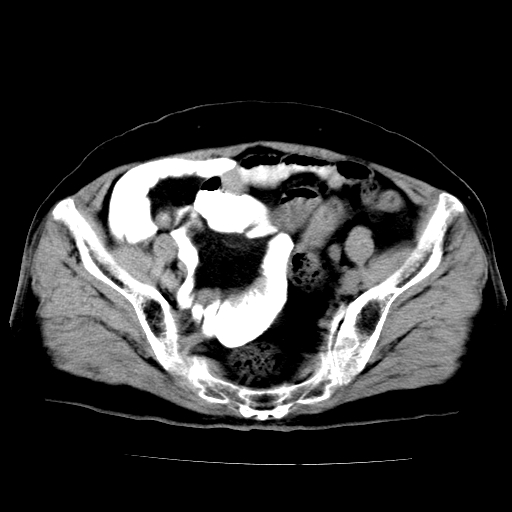

女,73岁,阴道流血一周。

宫颈不规则增大;结合临床考虑宫颈癌。建议作mri检查

1\\老年妇女突发阴道流血,常见病考虑宫颈癌.本病例宫颈部显示形态不规则,密度欠均匀,支持考虑宫 颈癌,建议mri 或阴道超声坚持

2\\但是盆腔两侧尚未见到明显肿大淋巴结等转移征象

宫颈不规则增大,左后方可见结节状突起.支持宫颈癌.

宫颈壁明显增厚,左侧为甚,宫颈癌待排,建议宫颈涂片细胞学检查。

宫颈不规则增大,周围脂肪间隙毛糙,结合临床考虑宫颈癌,盆腔内未见肿大淋巴结。